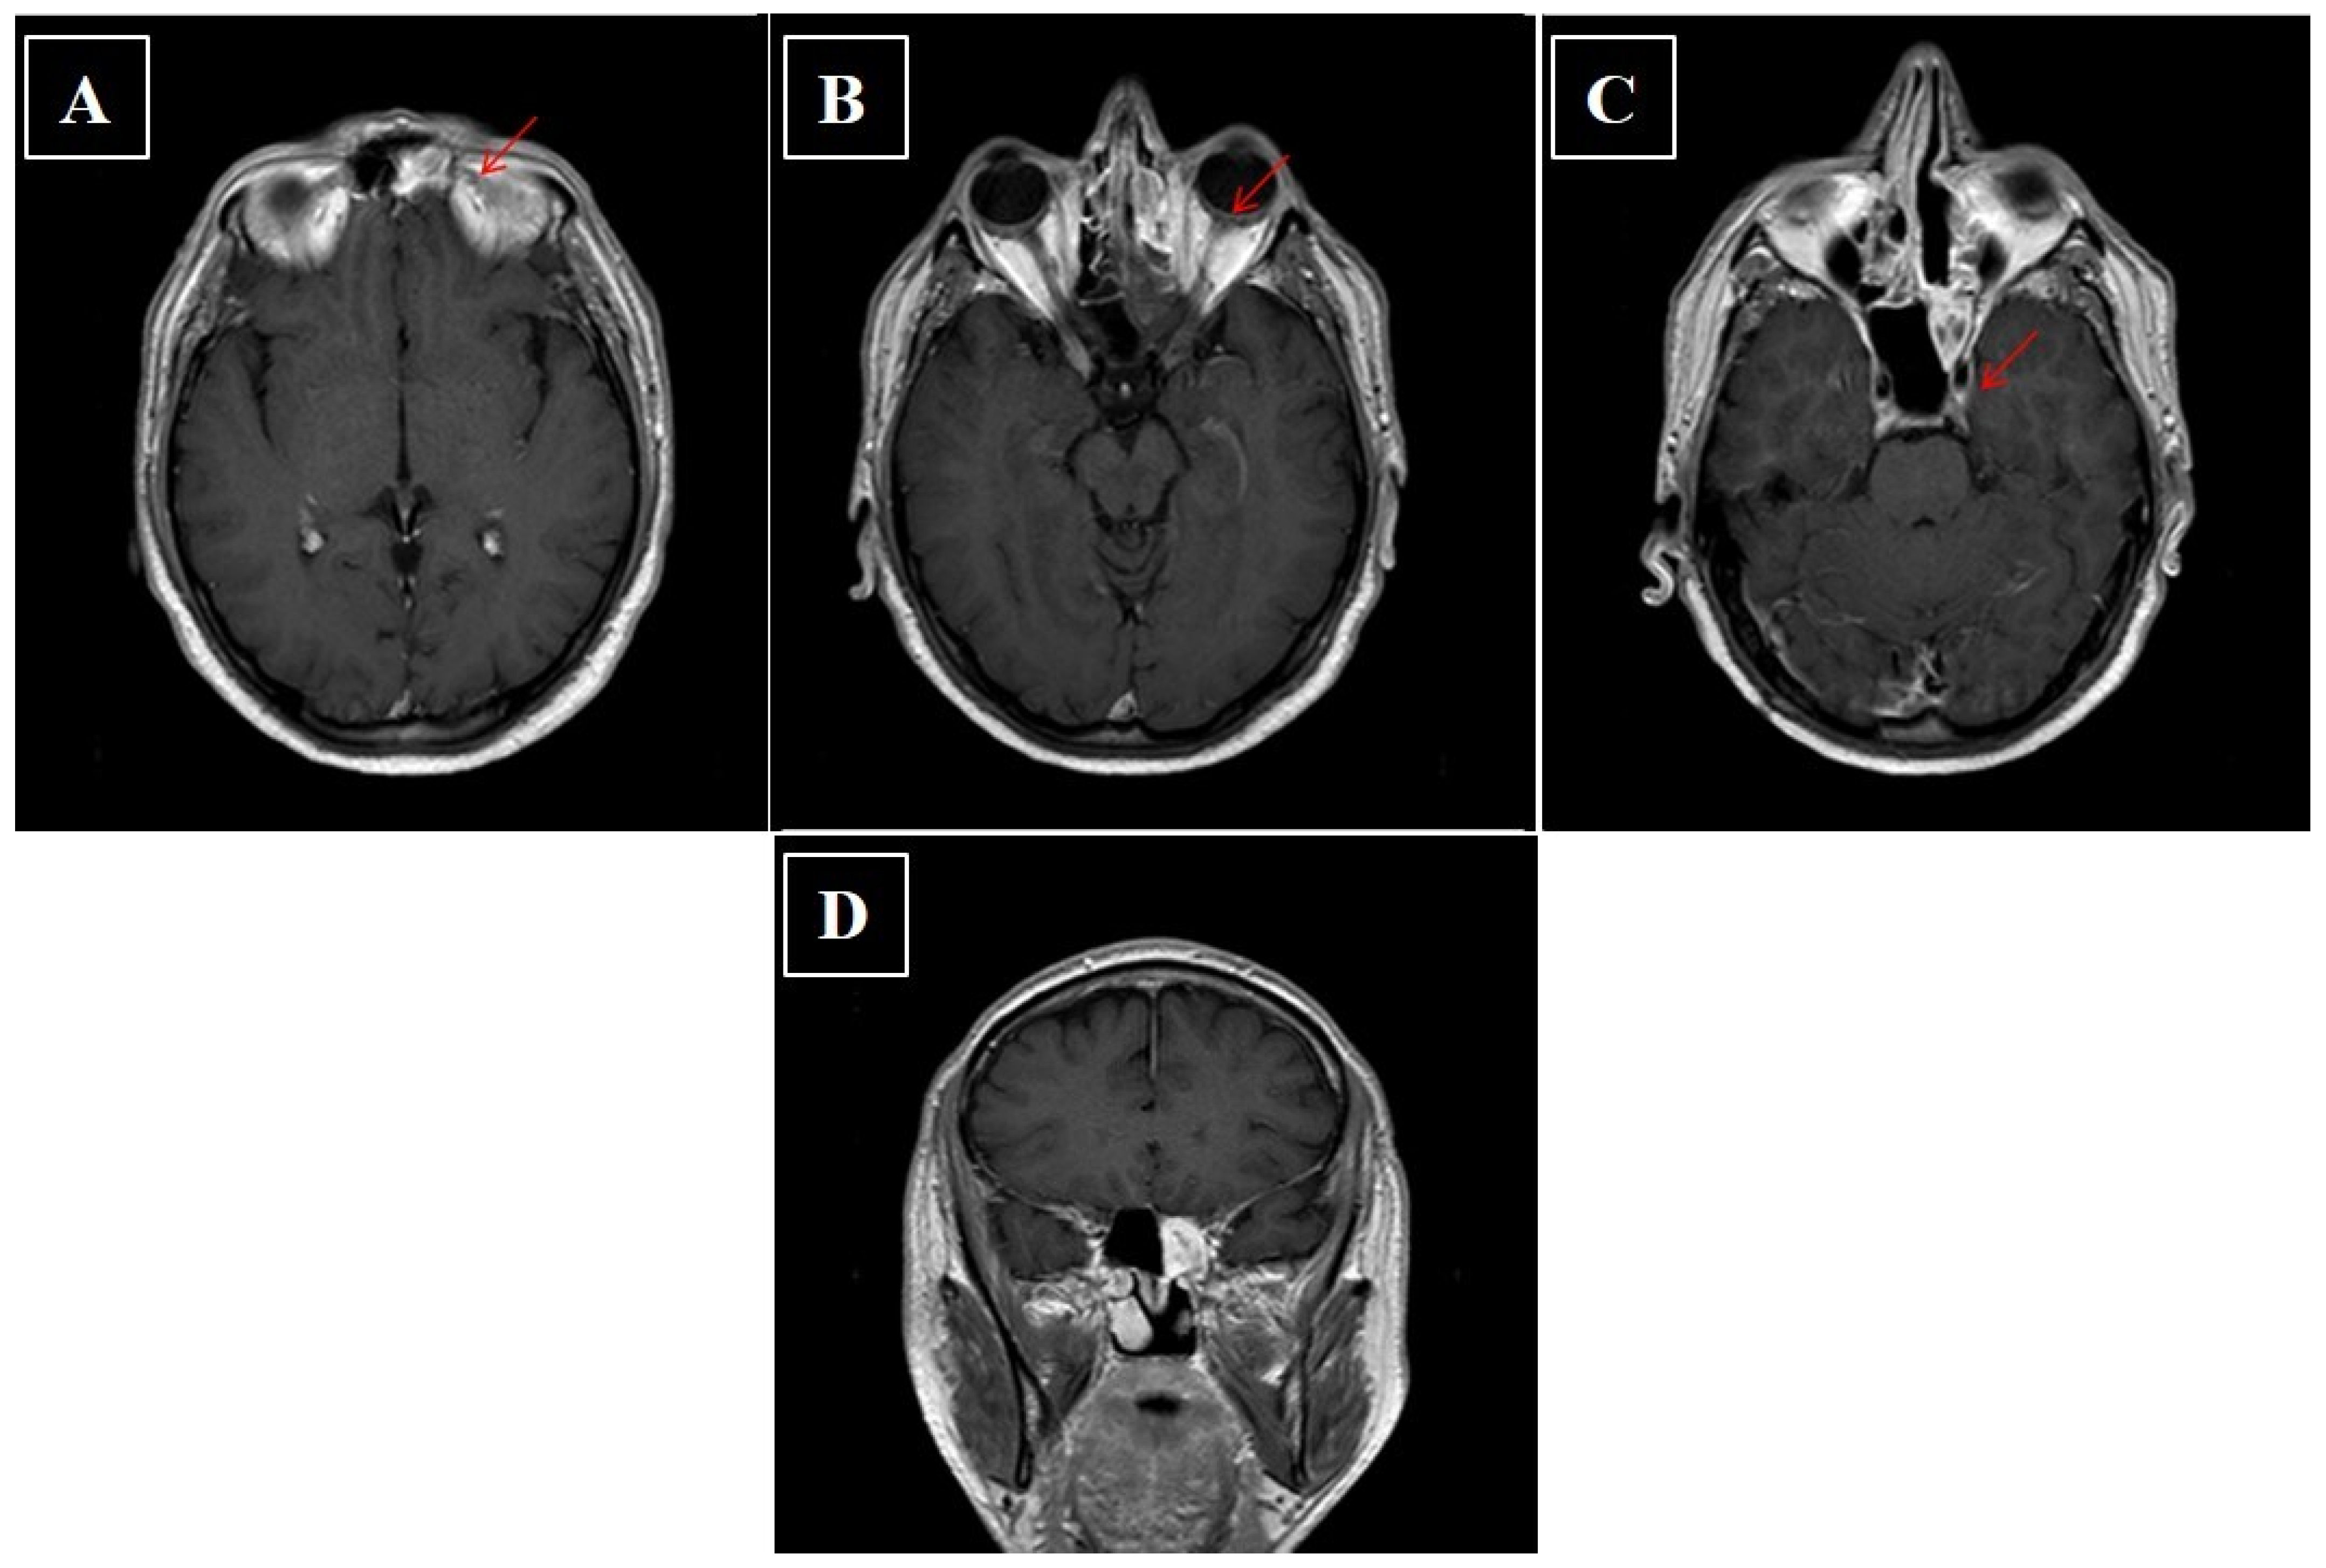

- Kawaguchi, M.; Kato, H.; Tomita, H.; Mizuta, K.; Aoki, M.; Hara, A.; Matsuo, M. Imaging Characteristics of Malignant Sinonasal Tumors. J. Clin. Med. 2017, 6, 116. [Google Scholar] [CrossRef]

- Sivalingam, J.; Sarawagi, R.; Raghuwanshi, S.; Yadav, P.K. Sinonasal Neoplasia – Clinicopathological Profile And Importance of Computed Tomography. J. Clin. Diagn. Res. 2015, 9, TC01–TC04. [Google Scholar] [CrossRef]

- Oztürk, E.; Sağlam, O.; Sönmez, G.; Cüce, F.; Haholu, A. CT and MRI of an unusual intranasal mass: Pleomorphic adenoma. Diagn. Interv. Radiol. 2008, 14, 186–188. [Google Scholar] [PubMed]